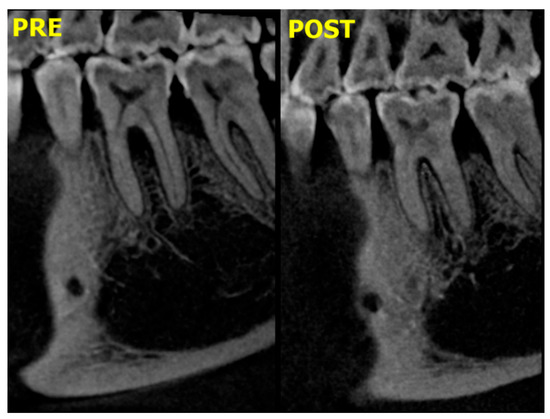

3.2. Radiographic Results

| Pre | Post | ||

| Group I | 13.79 ± 4.45 | 7.18 ± 2.8 | 0.002 |

| Group II | 6.23 ± 1.5 | 3.99 ± 0.52 | 0.008 |

| p-value | 0.003 * | ||